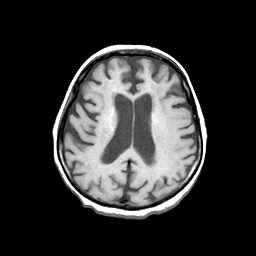

Basal Ganglia Calcification: T1-weighted MR -- Slice #11

[Home][Help][Clinical] Slice 11